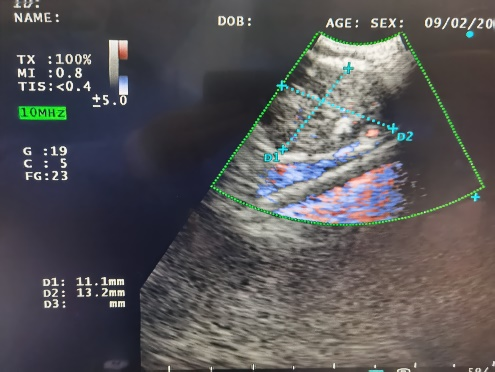

患者,女,50岁,因“反复咳嗽、气短半年,加重7日”入院。患者半年前辗转省市多家医院,甚至专科医院建议抗结核治疗4月,症状缓解不明显,在外院行2次支气管镜检查,均未能找到结核依据及确诊,后前来我院呼吸与危重症医学科一病区住院进一步诊治。入院后给予完善经支气管镜肺活检(TBLB)及超声引导下行经支气管针吸活检(EBUS-TBNA),病理诊断为结节病。

胸部CT:纵膈淋巴结肿大 双肺多发粟粒结节影

7组淋巴结肿大

4R组淋巴结肿大

病理诊断为结节病